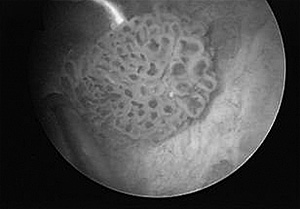

Το “Gold Standard” όμως είναι η ουρηθροκυστεοσκόπηση, όπου έχει τη δυνατότητα ο ουρολόγος να μπει στην κύστη με μια ειδική κάμερα. Στη συνέχεια, μπορεί να χρειαστούν περαιτέρω εξετάσεις όπως μια αξονική τομογραφία ή αξονική πυελογραφία.